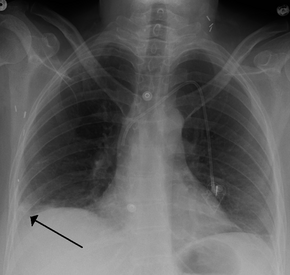

A Hampton hump in a person with a right lower lobe pulmonary embolism

In order to diagnose a pulmonary embolism, a review of clinical criteria to determine the need for testing is recommended.[24] In those who have low risk, age less than 50, heart rate less than 100 beats per minute, oxygen level more than 94% on room air, and no leg swelling, coughing up of blood, surgery or trauma in the last four weeks, previous blood clots, or estrogen use, further testing is not typically needed.[25]

• Chest X-rays are often done on people with shortness of breath to help rule-out other causes, such as congestive heart failure and rib fracture. Chest X-rays in PE are rarely normal,[59] but usually lack signs that suggest the diagnosis of PE (for example, Westermark sign, Hampton's hump).